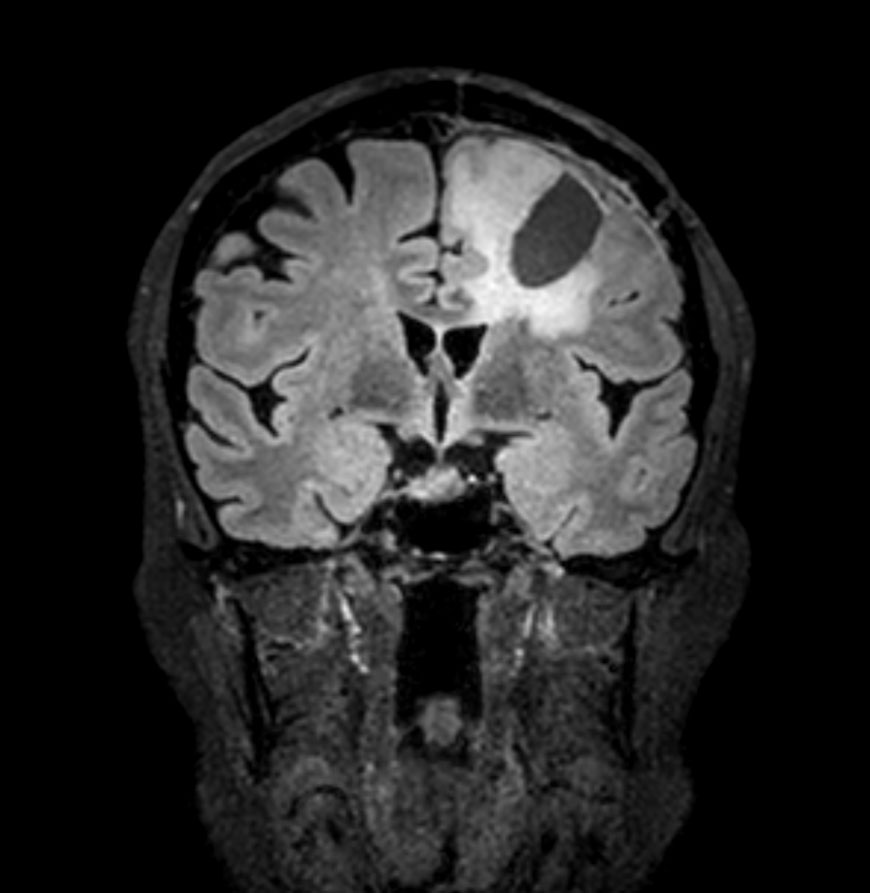

Sagittal 3D FLAIR

-

3D FLAIR - Coronal reformat

3D FLAIR - Axial reformat